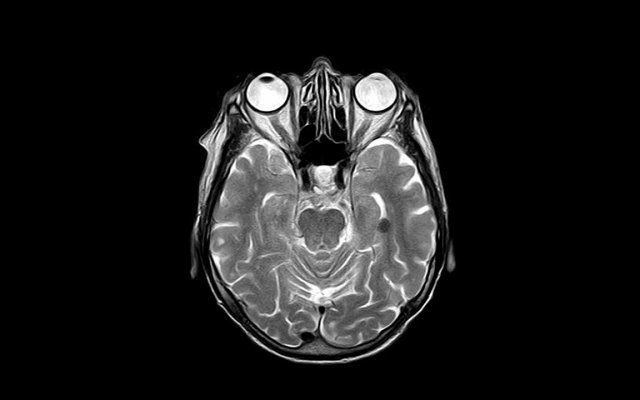

Une étude britannique, publiée dans Nature Medicine, suggère que la maladie d’Alzheimer pourrait être transmissible dans certains cas. L'hormone de croissance extractive, prélevée sur des humains décédés et administrée à des patients, est mise en cause.

L'équipe de John Collinge de l’Institut des maladies à prions de l’University College de Londres (UCL) a examiné cinq patients ayant reçu ces hormones avant 1985. Ces individus ont été diagnostiqués avec une forme atypique d’Alzheimer, liée à ce traitement. L’étude de l'UCL indique que la maladie de Creutzfeldt-Jakob (MCJ), transmise par les hormones de croissance, a entraîné la mort de 4% des 1.849 jeunes patients britanniques traités. Huit patients ont développé précocement la maladie d’Alzheimer. Trois sont décédés entre 47 et 57 ans et cinq ont entre 54 et 57 ans. Le seul lien entre ces huit patients était l’administration d’hormones de croissance.

Cela suggère que l’Alzheimer pourrait se transmettre comme les maladies à prions incurables, telles que la MCJ. Ces maladies sont caractérisées par le mauvais repliement d’une protéine, entraînant une réaction en chaîne sur les cellules et des dégâts dans le système nerveux central. L’Alzheimer est aussi caractérisée par les dommages causés par une protéine mal repliée, le peptide amyloïde bêta et une autre appelée Tau.

Cette étude confirme un lien possible entre ces deux groupes de maladies. Pour les chercheurs britanniques, la transmission d’Alzheimer serait “iatrogénique” (c’est-à-dire provoquée par un acte médical) en l’occurrence l’injection d’hormones de croissance. Cela suggère que cette maladie dégénérative pourrait être transmissible autrement que par l’hérédité.